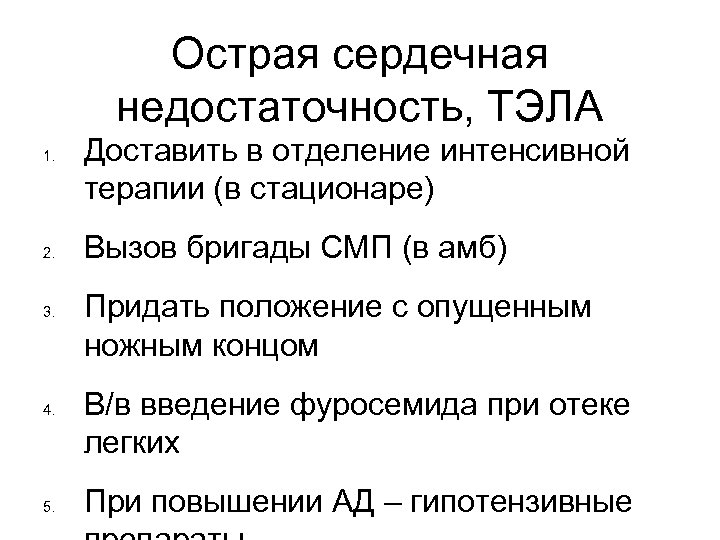

Острая сердечная недостаточность, ТЭЛА 1. 2. 3. 4. 5. Доставить в отделение интенсивной терапии (в стационаре) Вызов бригады СМП (в амб) Придать положение с опущенным ножным концом В/в введение фуросемида при отеке легких При повышении АД – гипотензивные

Острая сердечная недостаточность, ТЭЛА 1. 2. 3. 4. 5. Доставить в отделение интенсивной терапии (в стационаре) Вызов бригады СМП (в амб) Придать положение с опущенным ножным концом В/в введение фуросемида при отеке легких При повышении АД – гипотензивные